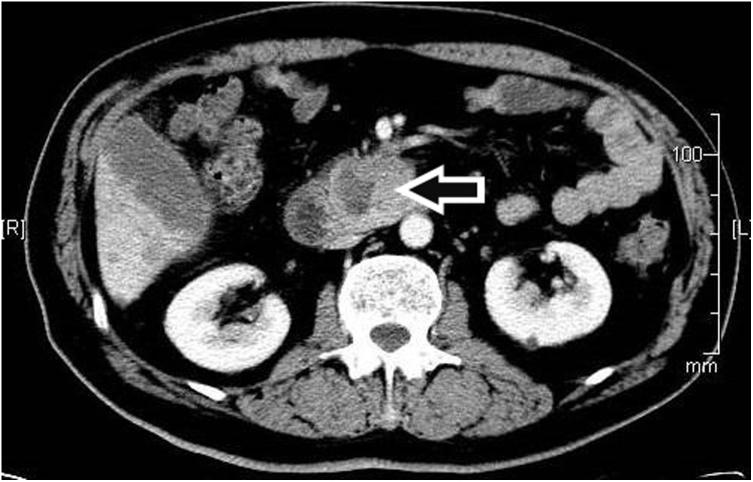

On univariate analysis, a solid component (p < 0.01), septation (p < 0.01), location (p < 0.01), border (p < 0.01), wall enhancement (p = 0.01), lesion margins (p < 0.01), pancreatic atrophy (p = 0.04), and a cystic wall (p < 0.01) were all significantly different between benign and premalignant or malignant cysts. On multivariate analysis, only a solid component (p < 0.01) and septation (p < 0.01) were significant.

A thin cystic wall, uniform homogeneity, a clear border, the presence of septation, pancreatic atrophy, and the absence of both wall enhancements and solid components were more frequently seen in benign cysts. A thick wall, lack of homogeneity, the presence of wall enhancements and solid components, absence of septation, only a small degree of pancreatic atrophy, and unclear borders were more frequent among premalignant or malignant cysts. The only CT features to differentiate benign from premalignant or malignant cysts were a solid component and septation.

单因素分析显示,实性成分(p<0.01)、分隔(p<0.01)、位置(p<0.01)、边界(p<0.01)、壁强化(p=0.01)、病变边缘(p<0.01)、胰腺萎缩(p=0.04)和囊壁(p<0.01)在良性囊肿与癌前或恶性囊肿之间均存在显著差异。多因素分析显示,只有实性成分(p<0.01)和分隔(p<0.01)具有显著性。

良性囊肿更常表现为薄壁、均匀一致、边界清晰、存在分隔、胰腺萎缩,且无壁强化和实性成分。癌前或恶性囊肿更常表现为厚壁、不均匀、存在壁强化和实性成分、无分隔、仅有轻度胰腺萎缩以及边界不清。区分良性囊肿与癌前或恶性囊肿的唯一CT特征是实性成分和分隔。